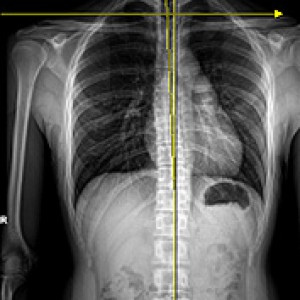

▲ 힘 전달의 균형 유지

▲ 힘 전달의 균형이 깨질 때

성인의 80%~90%에서 골반 부정렬이 발견되었으며,

그 중 3분의 1은 무증상, 3분의 2는 요통, 골반통 등의 증상을 호소한다.

Wolf Schamberger - The Malalignment Syndrome 中